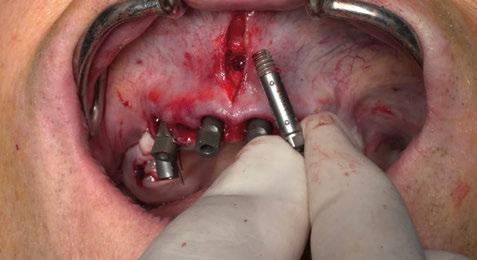

Figura 4. Intervención quirúrgica del caso clínico 1. a) posición del injerto suturado a través del colgajo de acceso apical vestibular; b) utilización de aloinjerto particulado (OraGRAFT® Aloinjerto Cortical Particulado MIX 70% Mineralizado / 30% Desmineralizado) para rellenar el interior del defecto y cubrir la dehiscencia ósea; c) cobertura de la dehiscencia ósea con el aloinjerto particulado; d) customización de la lámina de cortical acorde a las características del defecto (Lámina de cortical desmineralizada Cortiflex® Salugraft Dental).

Una vez preparado el lecho receptor, dada la existencia de una situación combinada de recesión gingival y una dehiscencia ósea vestibular con pérdida de inserción interproximal, se opta por la utilización combinada de un injerto de tejido conectivo autólogo tuberositario, un sustituto de origen alogénico (Lámina de cortical desmineralizada Cortiflex® Salugraft Dental) que se fija mediante dos chinchetas a ambos lados, cubriendo un injerto óseo de origen alogénico particulado (OraGRAFT® Aloinjerto Cortical Particulado MIX 70% Mineralizado / 30% Desmineralizado). Primero se suturó el injerto de tejido conectivo autólogo al colgajo, después se colocaron las partículas

de injerto óseo y, posteriormente, se fijó la lámina cortical.

En este sentido, vuelve a realizarse el mismo protocolo de materiales que en el primer caso clínico. Es decir, en primer lugar se sutura un injerto de tejido conectivo al colgajo; posteriormente se utiliza un injerto óseo alogénico particulado (OraGRAFT® Aloinjerto Cortical Particulado MIX 70% Mineralizado / 30% Desmineralizado) para reconstruir la dehiscencia ósea además de preservar el escaso alveolo del diente extraído; y adicionalmente se utiliza la lámina de cortical desmineralizada (Lámina de cortical desmineralizada Cortiflex® Salugraft Dental).